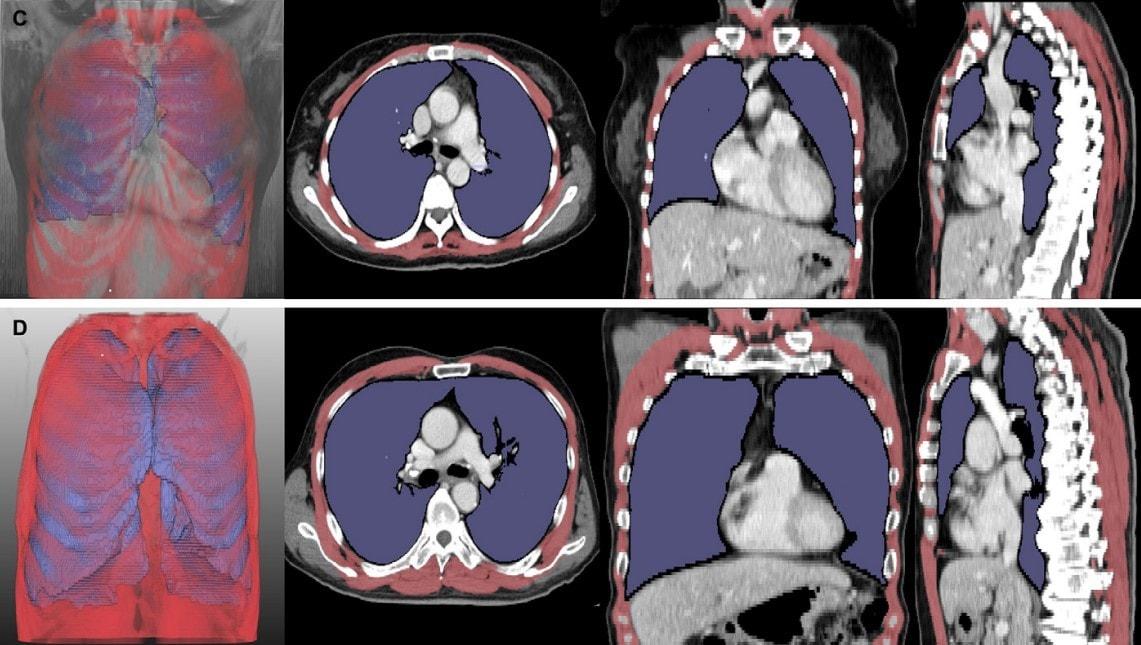

본문 이미지 - 루게릭병 환자의 흉부 CT 분석 결과(서울대병원 제공)

루게릭병 환자의 흉부 CT 분석 결과(서울대병원 제공)